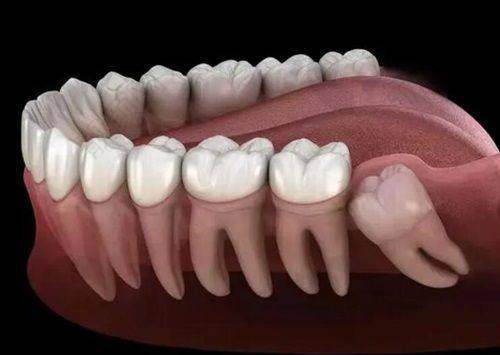

暨南雅皓口腔采用国内外多种精良的种植牙技术和设备。比如数字化导航种植、即刻种植等,这些技术可以提高手术的成功几率和患者的舒适度。医院还引进了齐全的口腔医疗设备,像CBCT全景机,拍片更清晰;显微根管仪,治疗更稳准;数字化种植导板,种牙更安心。这些设备为种植牙手术提供了高精度的数据支持,让种牙过程更加精细、安心。